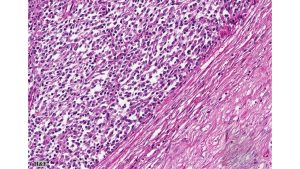

Histologic examination revealed densely cellular fascicles of monomorphic spindle cells with indistinct borders, oval nuclei and scant cytoplasm. The background showed necrosis and areas of hemorrhage. Immunohistochemical analysis revealed tumor cells positive for vimentin, CD99, BCL-2 and TLE1, while negative for CEA, EMA, desmin, chromogranin, synaptophysin, enolase, S-100, CD10, CD117, Caldesmon, beta-catenin, PAX2, and WT-1.

Primary synovial sarcoma of the kidney is exceedingly rare and often presents a diagnostic challenge due to morphologic overlap with other renal spindle cell tumors, such as sarcomatoid renal cell carcinoma, sarcomatoid urothelial carcinoma, and other primary renal sarcomas (e.g., leiomyosarcoma or malignant peripheral nerve sheath tumor). The monophasic spindle cell variant lacks epithelial components, making differentiation particularly difficult without molecular testing. Immunohistochemistry often demonstrates expression of TLE1, CD99, vimentin, and BCL-2, but these markers are not entirely specific. The definitive diagnosis hinges on detecting the characteristic t(X;18)(p11;q11) translocation, which results in the SS18-SSX fusion (typically SSX1 or SSX2) via FISH or RT-PCR.. These tumors tend to behave aggressively, with potential for local recurrence and distant metastasis, particularly to the lungs and liver. Long-term follow-up is essential, and optimal management often requires a multidisciplinary approach, incorporating surgery and consideration of systemic therapy in selected cases.